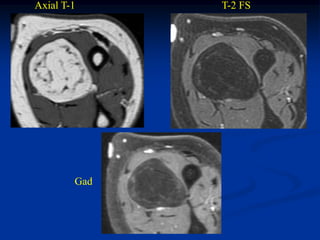

Case #270.2           Axial T-1             T-2

Gad

56 year male with painless soft

mass in anterior thigh for 2 years